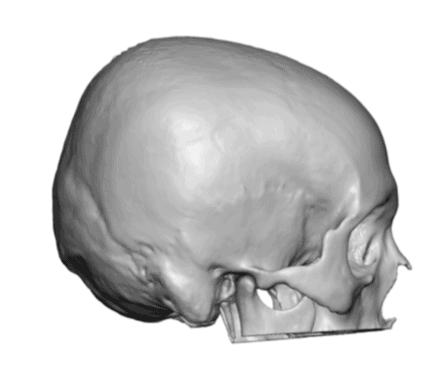

Desire for a higher and more prominent crown of the skull.

Crown of skull augmentation using a custom skull implant.

Desire for a higher and more prominent crown of the skull.

Crown of skull augmentation using a custom skull implant.